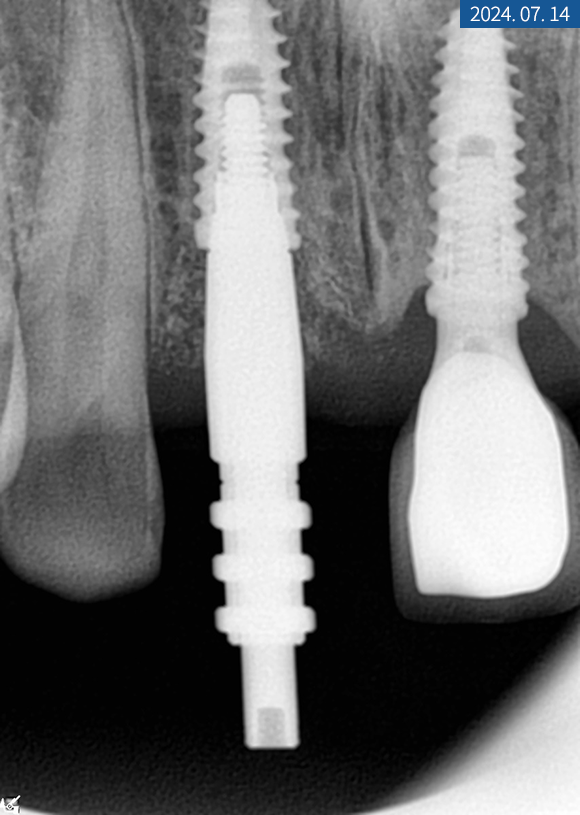

한 달 후 치근단 사진을 찍어보니

주위 염증 없이 이식된 자리에

잘 위치하고 있었습니다.

#11번은 인공 나사를 심고 힐링 어버트먼트를

바로 연결해서 잇몸을 만들었습니다.

3개월 후 골 유착을 확인하고

교합과 인상 채득을 한 다음 크라운 제작을 위해

색상 대조 후 기공소에 의뢰했습니다.